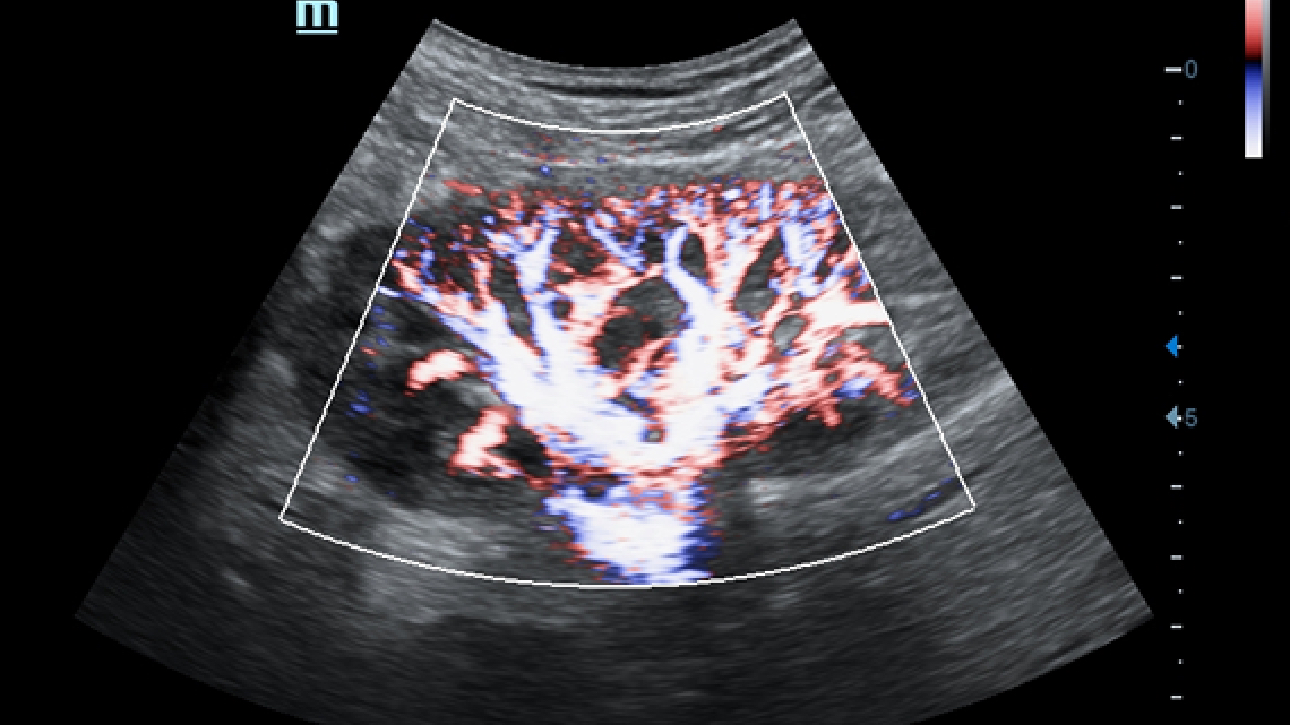

Obrazy kliniczne